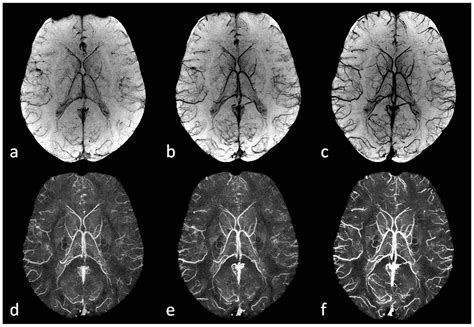

At its core, Susceptibility Weighted Imaging relies on the principle that various biological substances possess different magnetic susceptibilities. When placed in a powerful magnetic field, substances like deoxyhemoglobin, ferritin, hemosiderin, and calcium distort the local magnetic field differently than surrounding healthy tissue. While standard MRI sequences might overlook these subtle variations, SWI captures them by utilizing both the magnitude and phase information from the MRI signal.

The technique produces an enhanced contrast that highlights venous blood and iron deposition. Deoxyhemoglobin, being paramagnetic, induces a local magnetic field shift, which SWI exploits to visualize the venous system in exquisite detail. This is often referred to as "venography" without the need for injected contrast agents, making it a safer and highly effective diagnostic method for patients with renal impairment or those who are sensitive to gadolinium.

Implementing Susceptibility Weighted Imaging requires specific hardware and software considerations. High-field MRI scanners, typically 3 Tesla or higher, are preferred because the susceptibility effect is more pronounced at higher field strengths. The acquisition involves 3D gradient-echo sequences with long echo times to maximize the phase shifts caused by the magnetic susceptibility differences.

Radiologists look for "blooming effects" on the images, where small, dark spots represent paramagnetic substances like blood products. Because the signal decay is accelerated in regions with high iron or deoxyhemoglobin content, these areas appear as dark, high-contrast signals. Interpreting these images requires an understanding of how to differentiate between normal venous blood and pathological hemorrhages. For instance, the presence of blood in deep brain nuclei versus the cortex can indicate vastly different underlying etiologies, such as hypertensive vasculopathy or cerebral amyloid angiopathy.